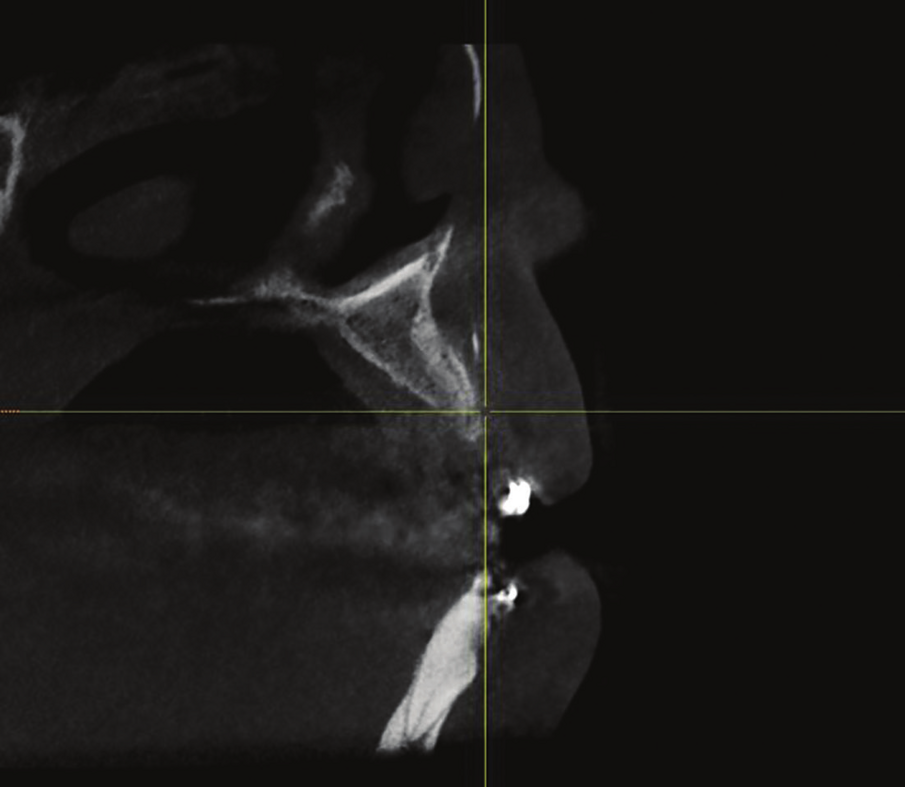

Figure 11: CBCT cross-sectional view of sites no 7 and 8 revealed inadequate ridge width to support implant with restoration.

Figure 12: Preoperative view showing the amount of horizontal bone deficiency in the area.

A 33 years-old male patient was visiting our clinic to replace missing teeth no 7 and 8. He was medically fit and mentioned that his teeth were lost due to car accident few years back. Intraoral examination shows absence of space for implant placement and restoration, orthodontic treatment was conducted for 18 sessions followed by surgical implant placement after stabilization of the occlusion. Following the restoration of the space, the amount of horizontal bone loss was evident both clinically and on CAT examinations (Fig.10, 11). A linear incision with mucoperiosteal flap elevation were conducted, the amount of horizontal bone loss was advanced (Fig. 12), which was an indication for autologous bone graft, patient refused to undergo an invasive surgery so PRF associated bovine bone was planned in the area. Blood withdrawal and centrifugation were done with preparation of both L-PRF membranes and sticky bone (bovine bone associated PRF) (Fig.13, 14,15). The combination was placed on the host bone deficiency and covered by a first layer of L-PRF membranes in order to stabilize the graft and insure hemostasis, the second layer of L-PRF membranes covered the cross linked collagen membrane placed in the same area and covering the first entity (Fig.16).